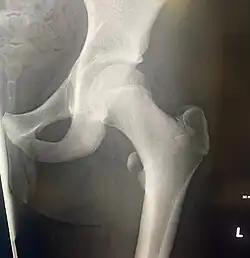

Left hip-joint, opened by removing the floor of the acetabulum from within the pelvis.

In human anatomy, the lesser trochanter is a conical, posteromedial, bony projection from the shaft of the femur. It serves as the principal insertion site of the iliopsoas muscle.[1]

The lesser trochanter is a conical posteromedial projection of the shaft of the femur, projecting from the posteroinferior aspect of its junction with the femoral neck.[1]

The intertrochanteric crest (which demarcates the junction of the femoral shaft and neck posteriorly) extends between the lesser trochanter and the greater trochanter on the posterior surface of the femur.[1]